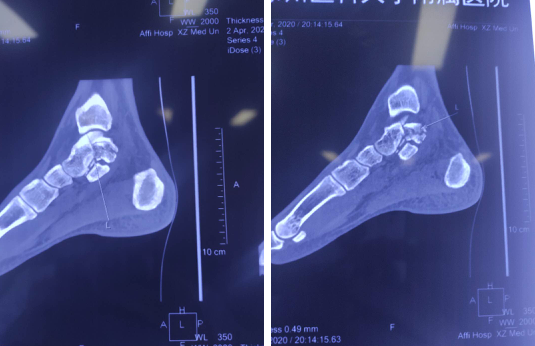

术前CT

足踝科二病区副主任徐明亮给患者检查发现,患者左距骨骨折,三角韧带、距腓前韧带、跟腓韧带损伤,需要做韧带修复和骨折复位手术。但是,“这个部位比较特殊,如果是传统切开手术的话,损伤比较大,后期距骨坏死的几率会比较高。”

徐主任和足踝科大科主任石荣剑主任医师讨论后,决定采取微创手术,进行踝关节镜下韧带修复;同时,在天玑骨科手术机器人的精准定位导航下,进行距骨骨折复位内固定手术,这样固定效果更好,损伤更小。

完善相关检查后,石院长徐主任手术团队为患者进行了关节镜下韧带修复术和机器人辅助下骨折固定术。首先利用踝关节镜探查距腓前韧带断裂,用可吸收带线锚钉修复;镜下探查复位保证距骨关节面平整;由机器人定位,精准地闭合平行打入两枚空心螺钉,骨折固定精准稳定。

整台手术完成时间不到2小时,手术时间缩短,手术微创性和精准性却大大提高。机器人为螺钉的置入提供精准的空间定位和稳定的路径,由于置入精度高,误差在0.8mm以下,在距骨形状复杂,螺钉通道狭长的情况下,准确实现了预定的内固定方案。